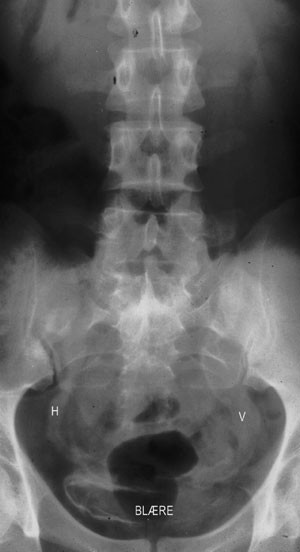

Bildet er et oversiktsrøntgenogram uten kontrast som viser et avansert stadium av schistosomiasis i urinveiene med utbredte veggforkalkninger i urinblæren og i utvidede urinledere (H, V). Mest utvidet er den venstre der forkalkningene følges opp til nivå med øvre rand av os sacrum.

Etter modning i leveren finner ormen veien til urinblærens venepleksus, noen ganger også til det hemoroidale. Generelle symptomer skyldes reaksjon på eggene. Et fremtredende lokalt symptom er hematuri. Eggene induserer en reaktiv fibroserende prosess i blære og uretre med kalknedslag. Dette fører til avløpshinder i urinlederne med komplikasjoner i form av steindanning, sekundær infeksjon og nyresvikt. Tilstanden disponerer også for blærecancer.